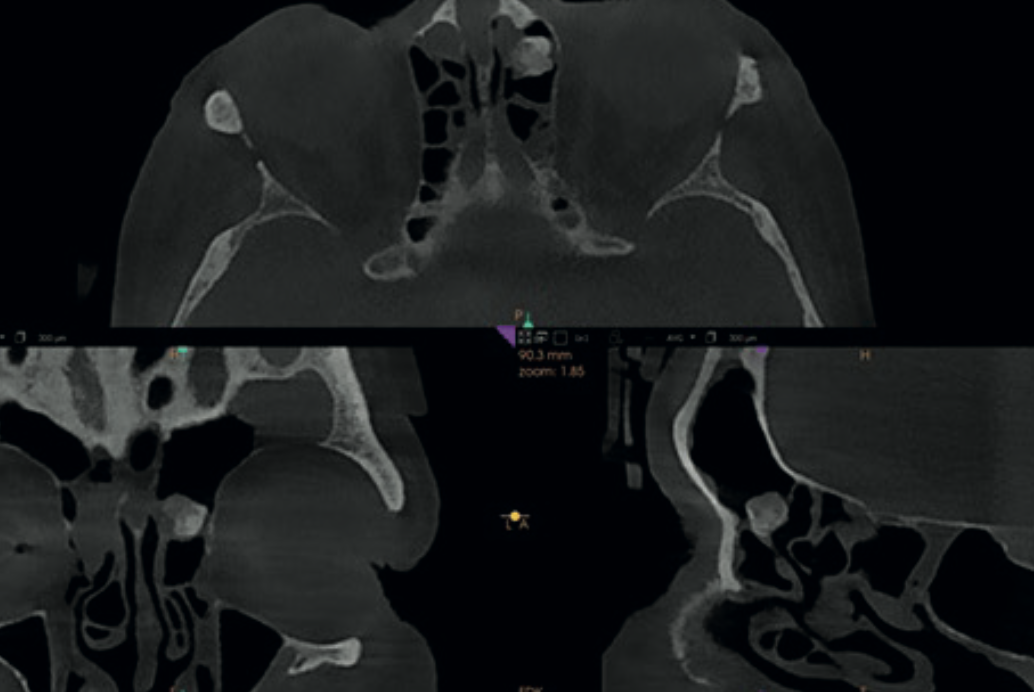

MPR views showing a well-defined bony lesion in the left anterior ethmoid cells — suspected osteoma

Finding 4

Ethmoid osteoma

A well-defined bony outgrowth in the left anterior ethmoid cells. Although benign, osteomas can grow and compromise sinus drainage — may require surgical removal.